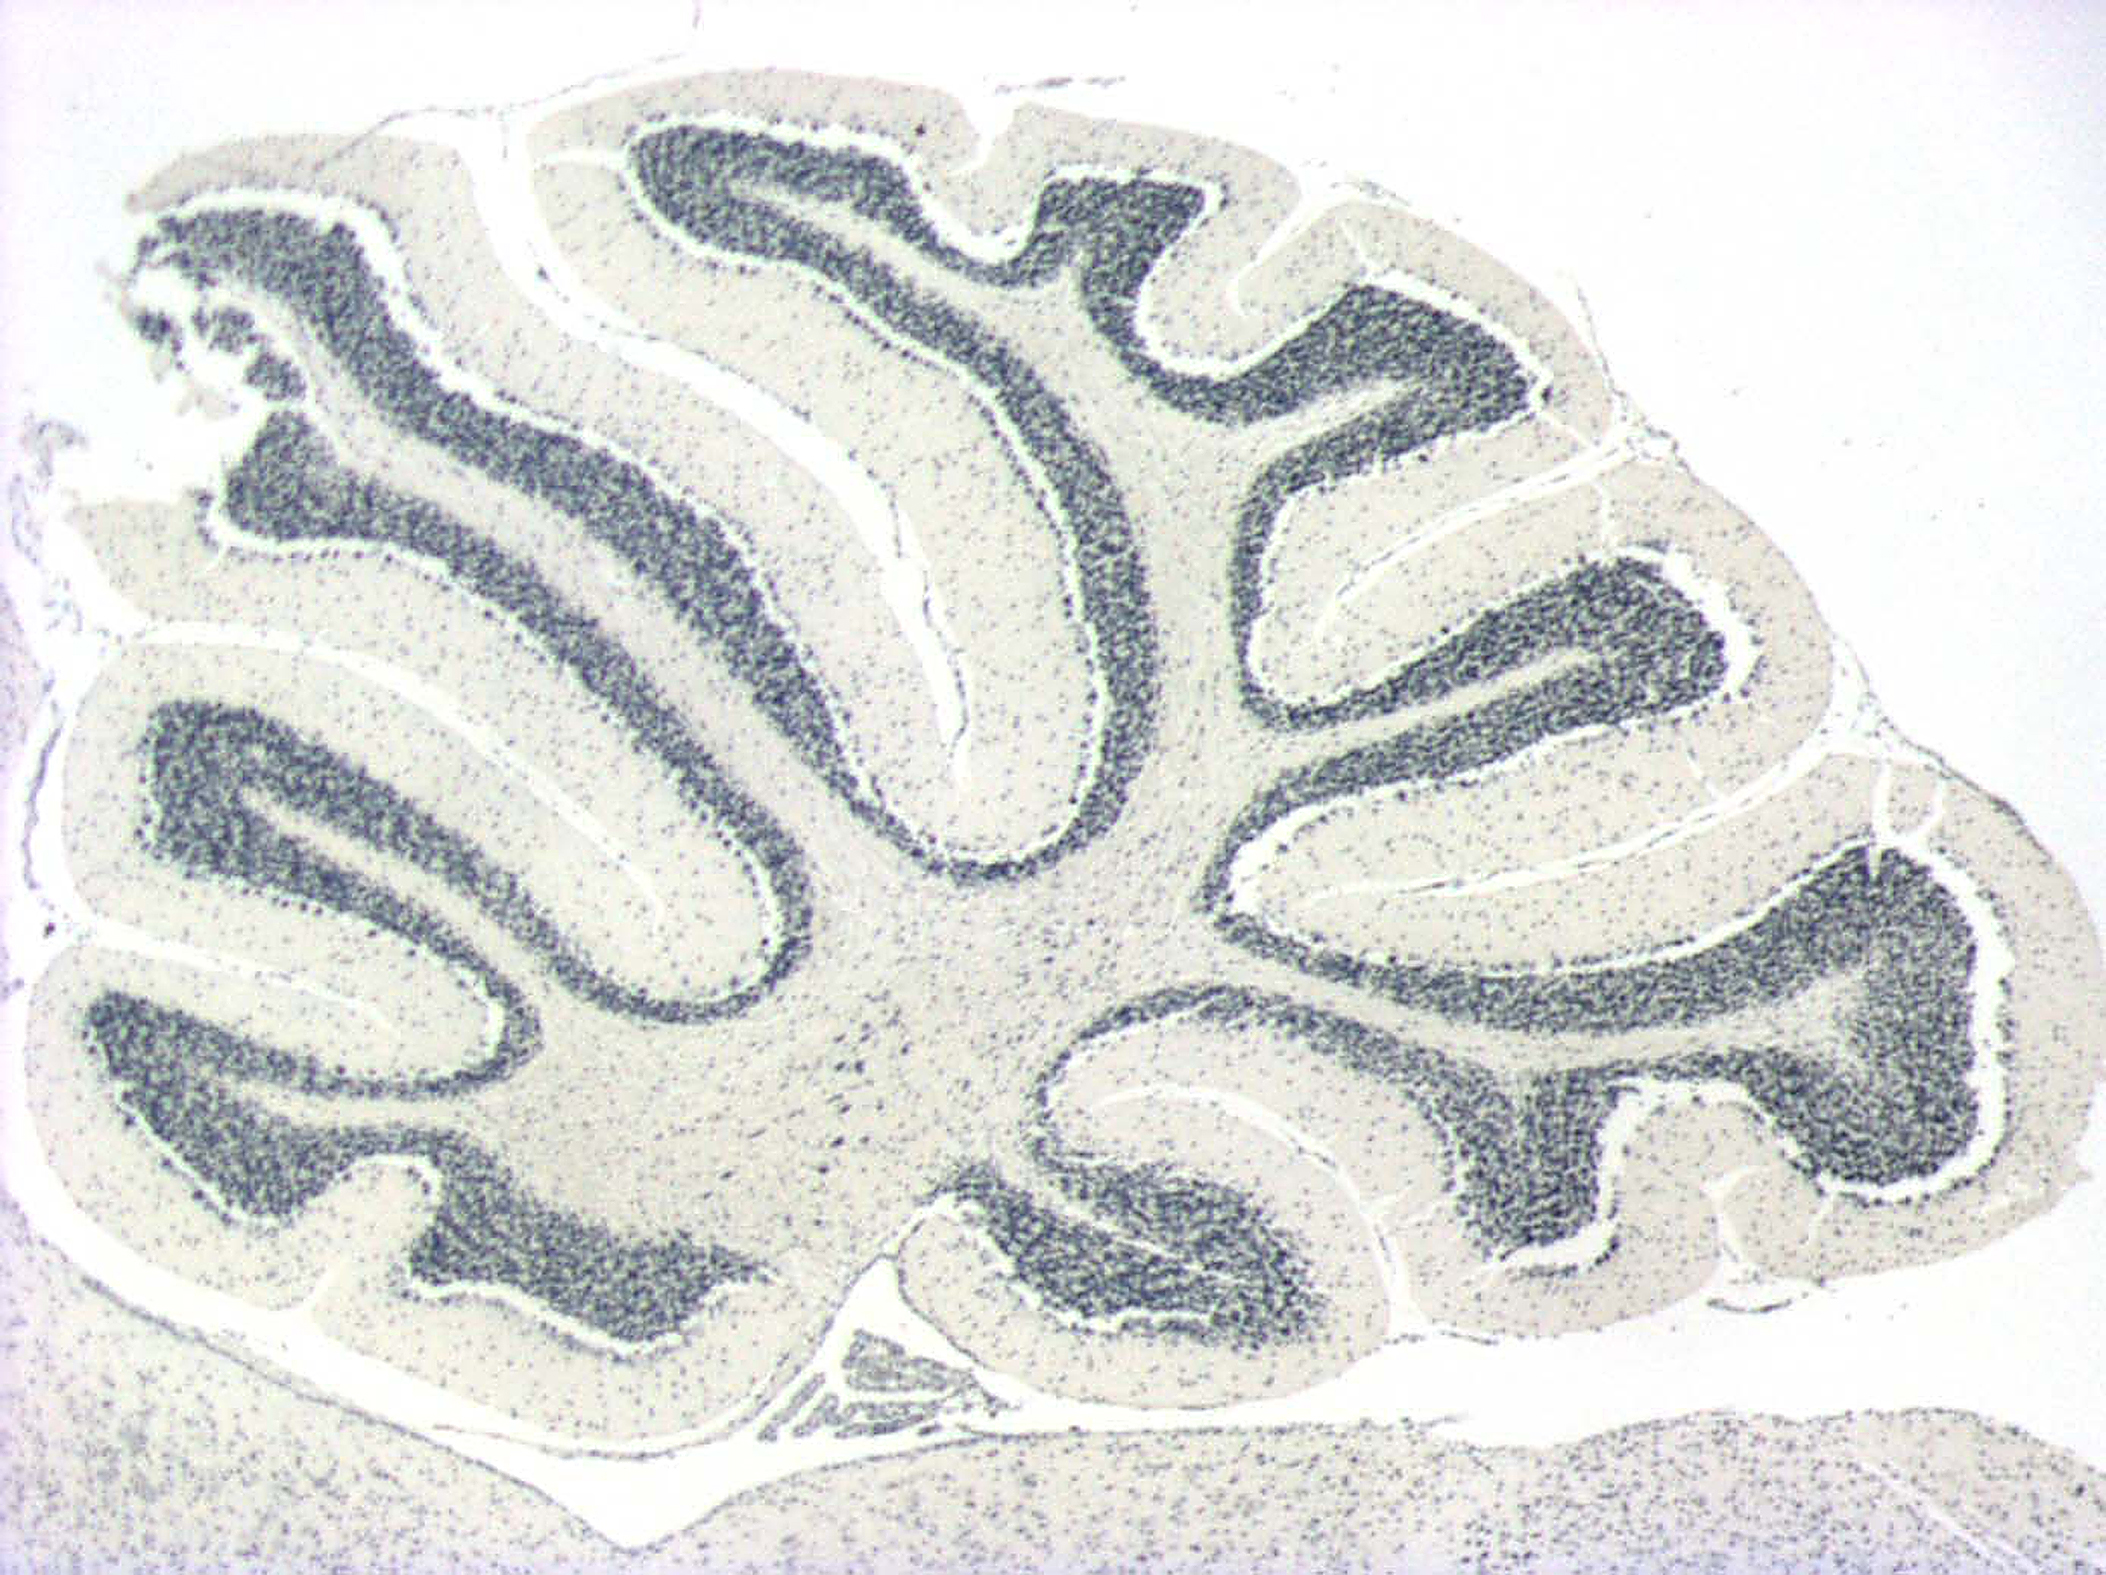

Coupe longitudinale de cervelet de souris (X50)

Coloration Hématoxyline